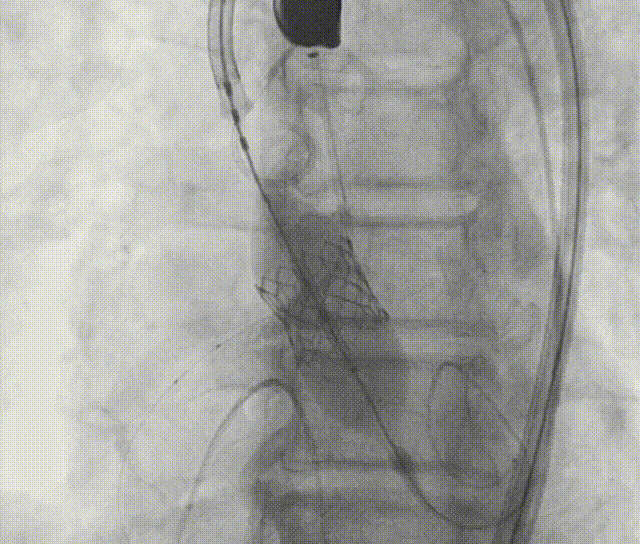

预扩未见右冠显影,球囊主动保护。

图片

通过支撑导丝,送入23mm SAPIEN 3瓣膜,使用独特调弯功能,保证安全过弓并成功跨瓣;调整至共平面角度,瓣膜到位,快速起搏下+1cc精准释放瓣膜。